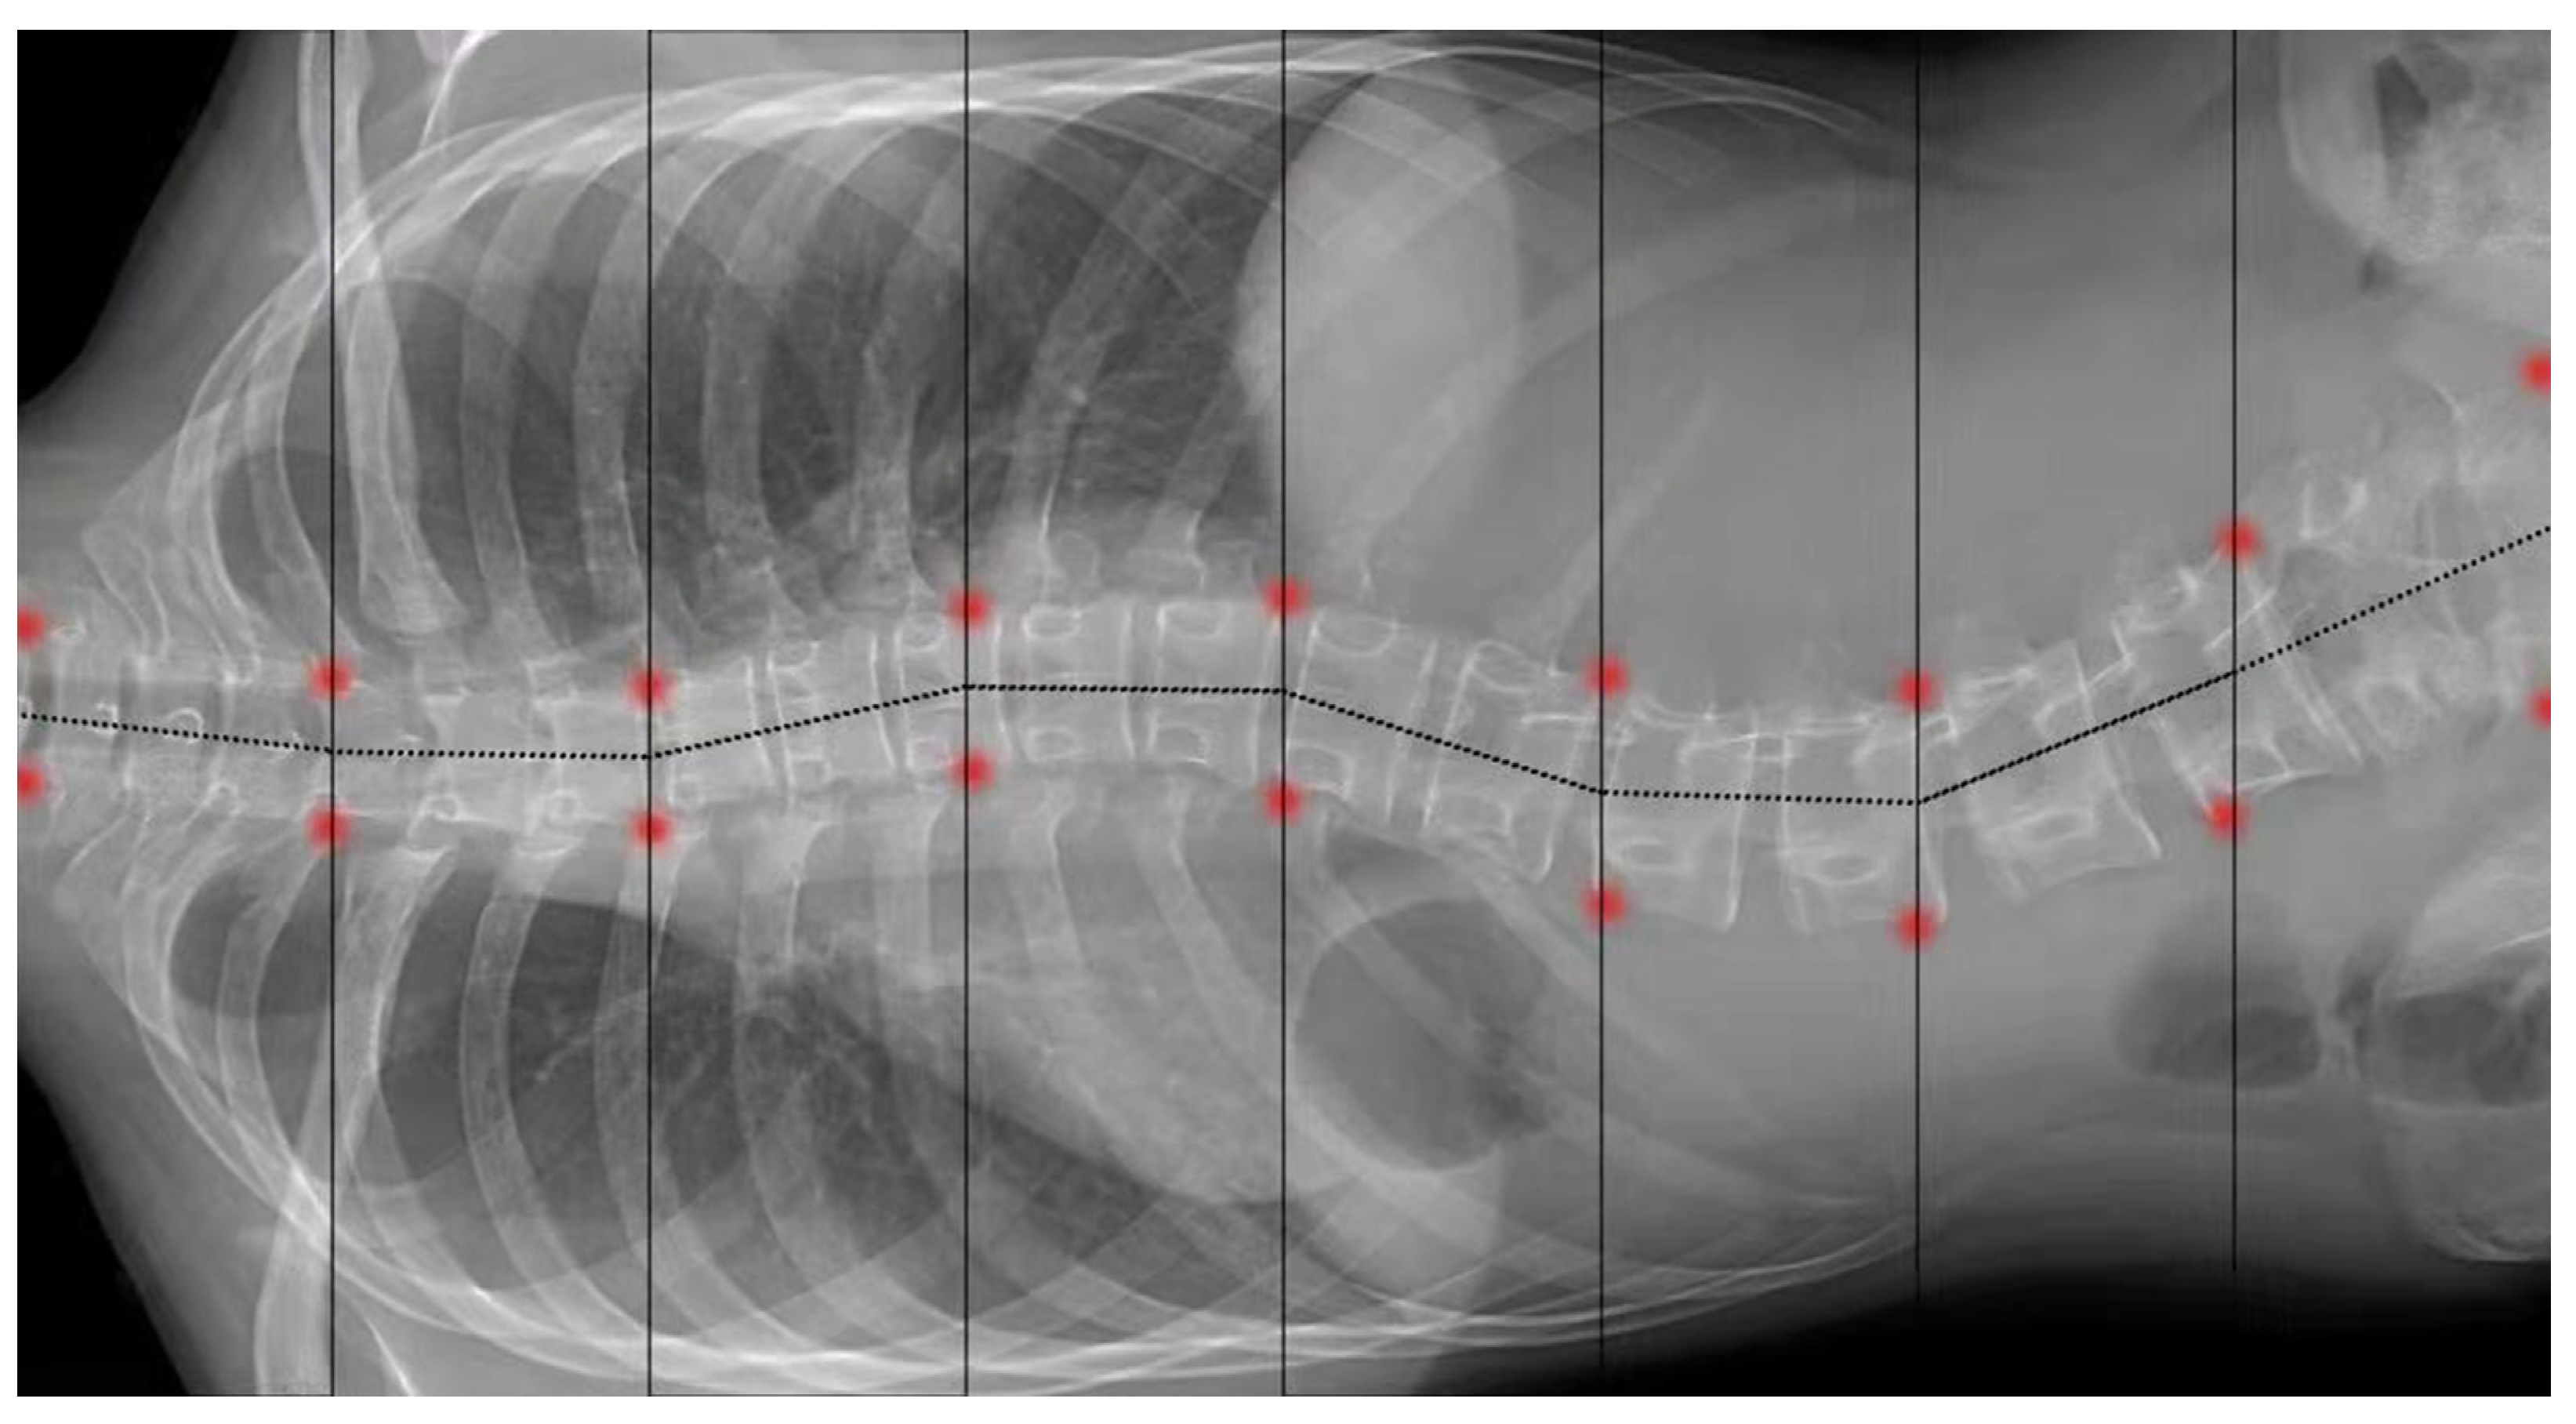

- Wang, L.; Traub, J.; Weidert, S.; Heining, S.M.; Euler, E.; Navab, N. Parallax-free intra-operative X-ray image stitching. Med. Image Anal. 2010, 14, 674–686. [Google Scholar] [CrossRef]

- Ellingson, A.M.; Boelter, K.; Sembrano, J.N.; Takahashi, T.; Polly, D.W. Intraoperative stitched fluoroscopic images: Effect of parallax on angular measurements of the spine. Spine J. 2022, 1–4. [Google Scholar] [CrossRef] [PubMed]